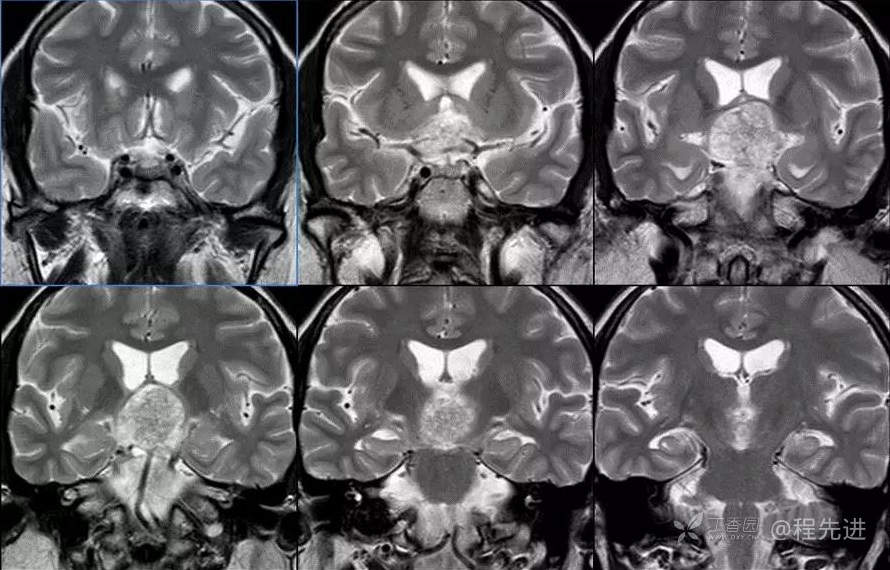

图像依次为T1横断位、T2横断位、T2FLAIR横断位、T2冠状、T1矢状、T1增强横断、矢状、冠状位